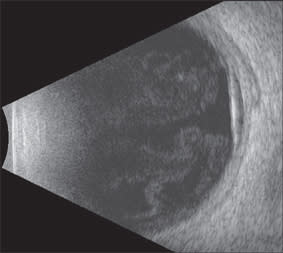

On examination, her vision was light perception in her right eye and barely counting fingers in her left eye. Anterior-segment examination revealed a 1-mm layered hypopyon in her right eye and 3+ cells in her left eye. Posteriorly, she had bilateral 3+ vitreous cells, arteriolar and venous sheathing, extensive intraretinal hemorrhage, retinal edema, and serous retinal detachments (Figure 1).

Figure 1. B-scan ultrasonography of the left eye, revealing significant vitritis, serous retinal detachment, and choroidal thickening. Evaluation of the right eye revealed similar findings.